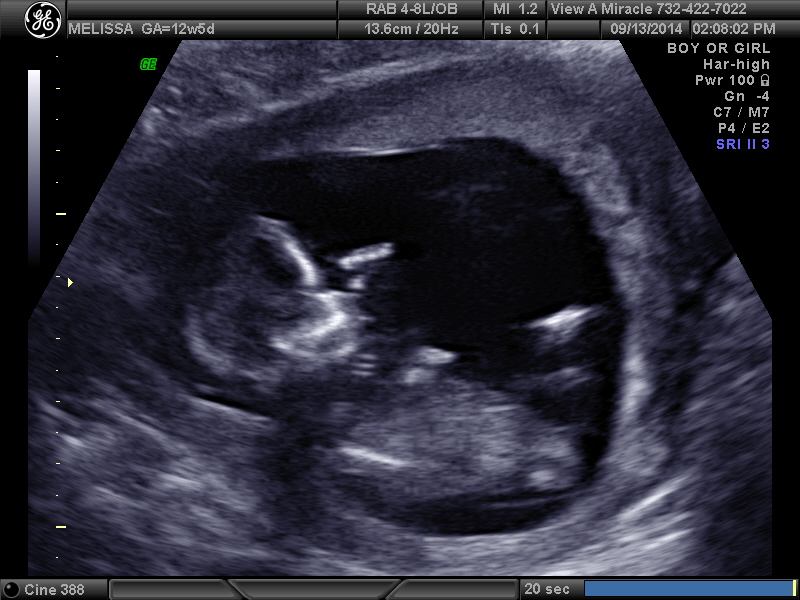

12 weeks 3 days. Tech told me girl and I'm over the moon but I think the potty shot looks like a boy... Opinions please!!!!

i got 2-3 more on a cd...

Attachment 20899

Hmmm. Honestly from these I'd say boy. It's still early though.